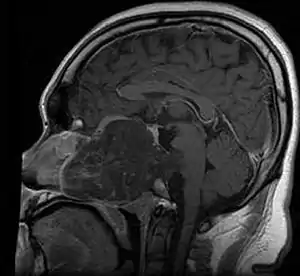

Chordoma is a rare slow-growing neoplasm thought to arise from cellular remnants of the notochord. The evidence for this is the location of the tumors (along the neuraxis), the similar immunohistochemical staining patterns, and the demonstration that notochordal cells are preferentially left behind in the clivus and sacrococcygeal regions when the remainder of the notochord regresses during fetal life.

Chordomas can arise from bone in the skull base and anywhere along the spine. The two most common locations are cranially at the clivus and in the sacrum at the bottom of the spine.[2]